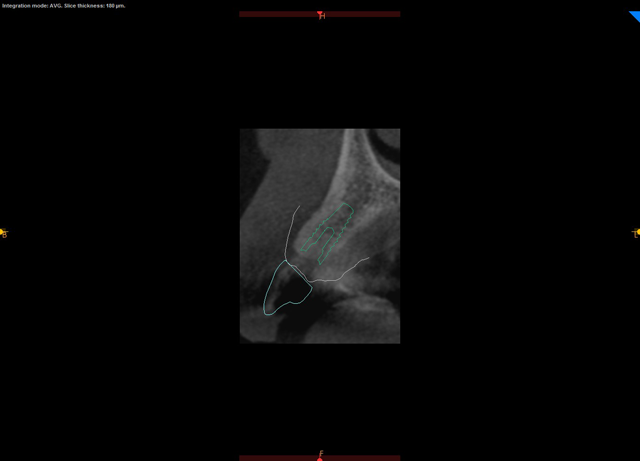

A CBCT scan was taken with a Carestream Dental CS 9300 (Figs. 2 and 3) and an intraoral scan was obtained using a Carestream Dental intraoral scanner (Figs. 4 and 5).

Fig. 3 Fig. 4

This technique starts with good diagnosis and treatment planning. Beginning with our clinical exam, we design our case with the end result in mind. A well-designed case, along with a well-designed provisional, will not only prepare the emergence profile prior to implant placement but will also assist the implant surgeon in choosing optimal implant position. When a cone beam computed tomography (CBCT) scan and a digital impression of the patient’s existing dentition are obtained, the goal is to create two files: the CBCT, which is a DICOM file, and the intraoral scanner file, which is in a STL format. We then merge those two files in an implant planning software to fabricate our guide and provisional restoration. If teeth are present, we can use these as guides to where we need to place our implants. If teeth are not present, then virtual teeth can be placed into the digital planning software so that implant position can be planned in an ideal location.